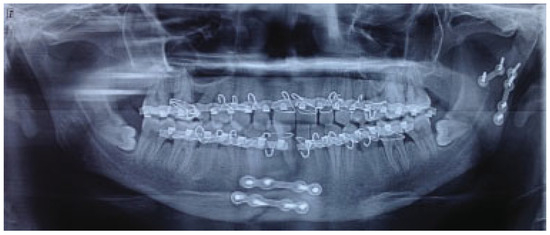

The mean for ramal height shortening was found to be 11.9 (0.99) preoperatively and 11.6 (1.57) postoperatively in Group A. It was compared using paired t-test and this difference was found not to be statistically significant (p = 0.34; Figure 1 and Figure 2). The mean for ramal height shortening was found to be 12.5 (0.84) preoperatively and (0.87) postoperatively in Group B. It was compared using paired t-test and this difference was found to be statistically significant (p < 0.05; Figure 3 and Figure 4).

Figure 1.

Group A: Preoperative orthopantomography showing left displaced subcondylar fracture and right parasymphysis fracture.

Figure 2.

Group A: Postoperative orthopantomography.